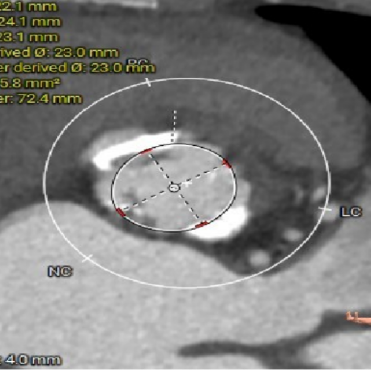

ANNULUS

图片